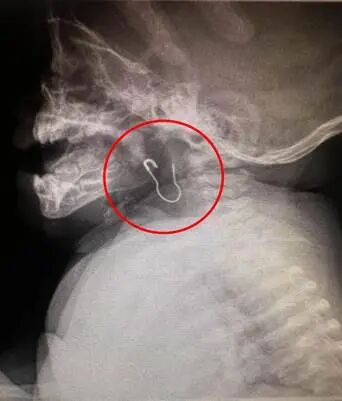

5月6日17点10分,一名7个月大的婴儿至中信惠州医院儿科就诊,儿科罗红志主任接诊,患儿监护人诉:误吞“金属曲别针”,患儿哭闹不止,罗红志主任判断情况危急,立即启动应急预案:组织耳鼻咽喉头颈外科、影像科、麻醉科多学科会诊,并第一时间开辟住院、手术绿色通道于17:40分进入中心手术室,行全麻下喉内异物取出术,经过耳鼻喉头颈外科王建设(主任医师)主刀及中心手术室团队的紧急施救,18: 00分完成手术,患儿转危为安,留观一夜。

(图:胸部正侧位片提示:舌骨水平气道区域金属异物滞留)